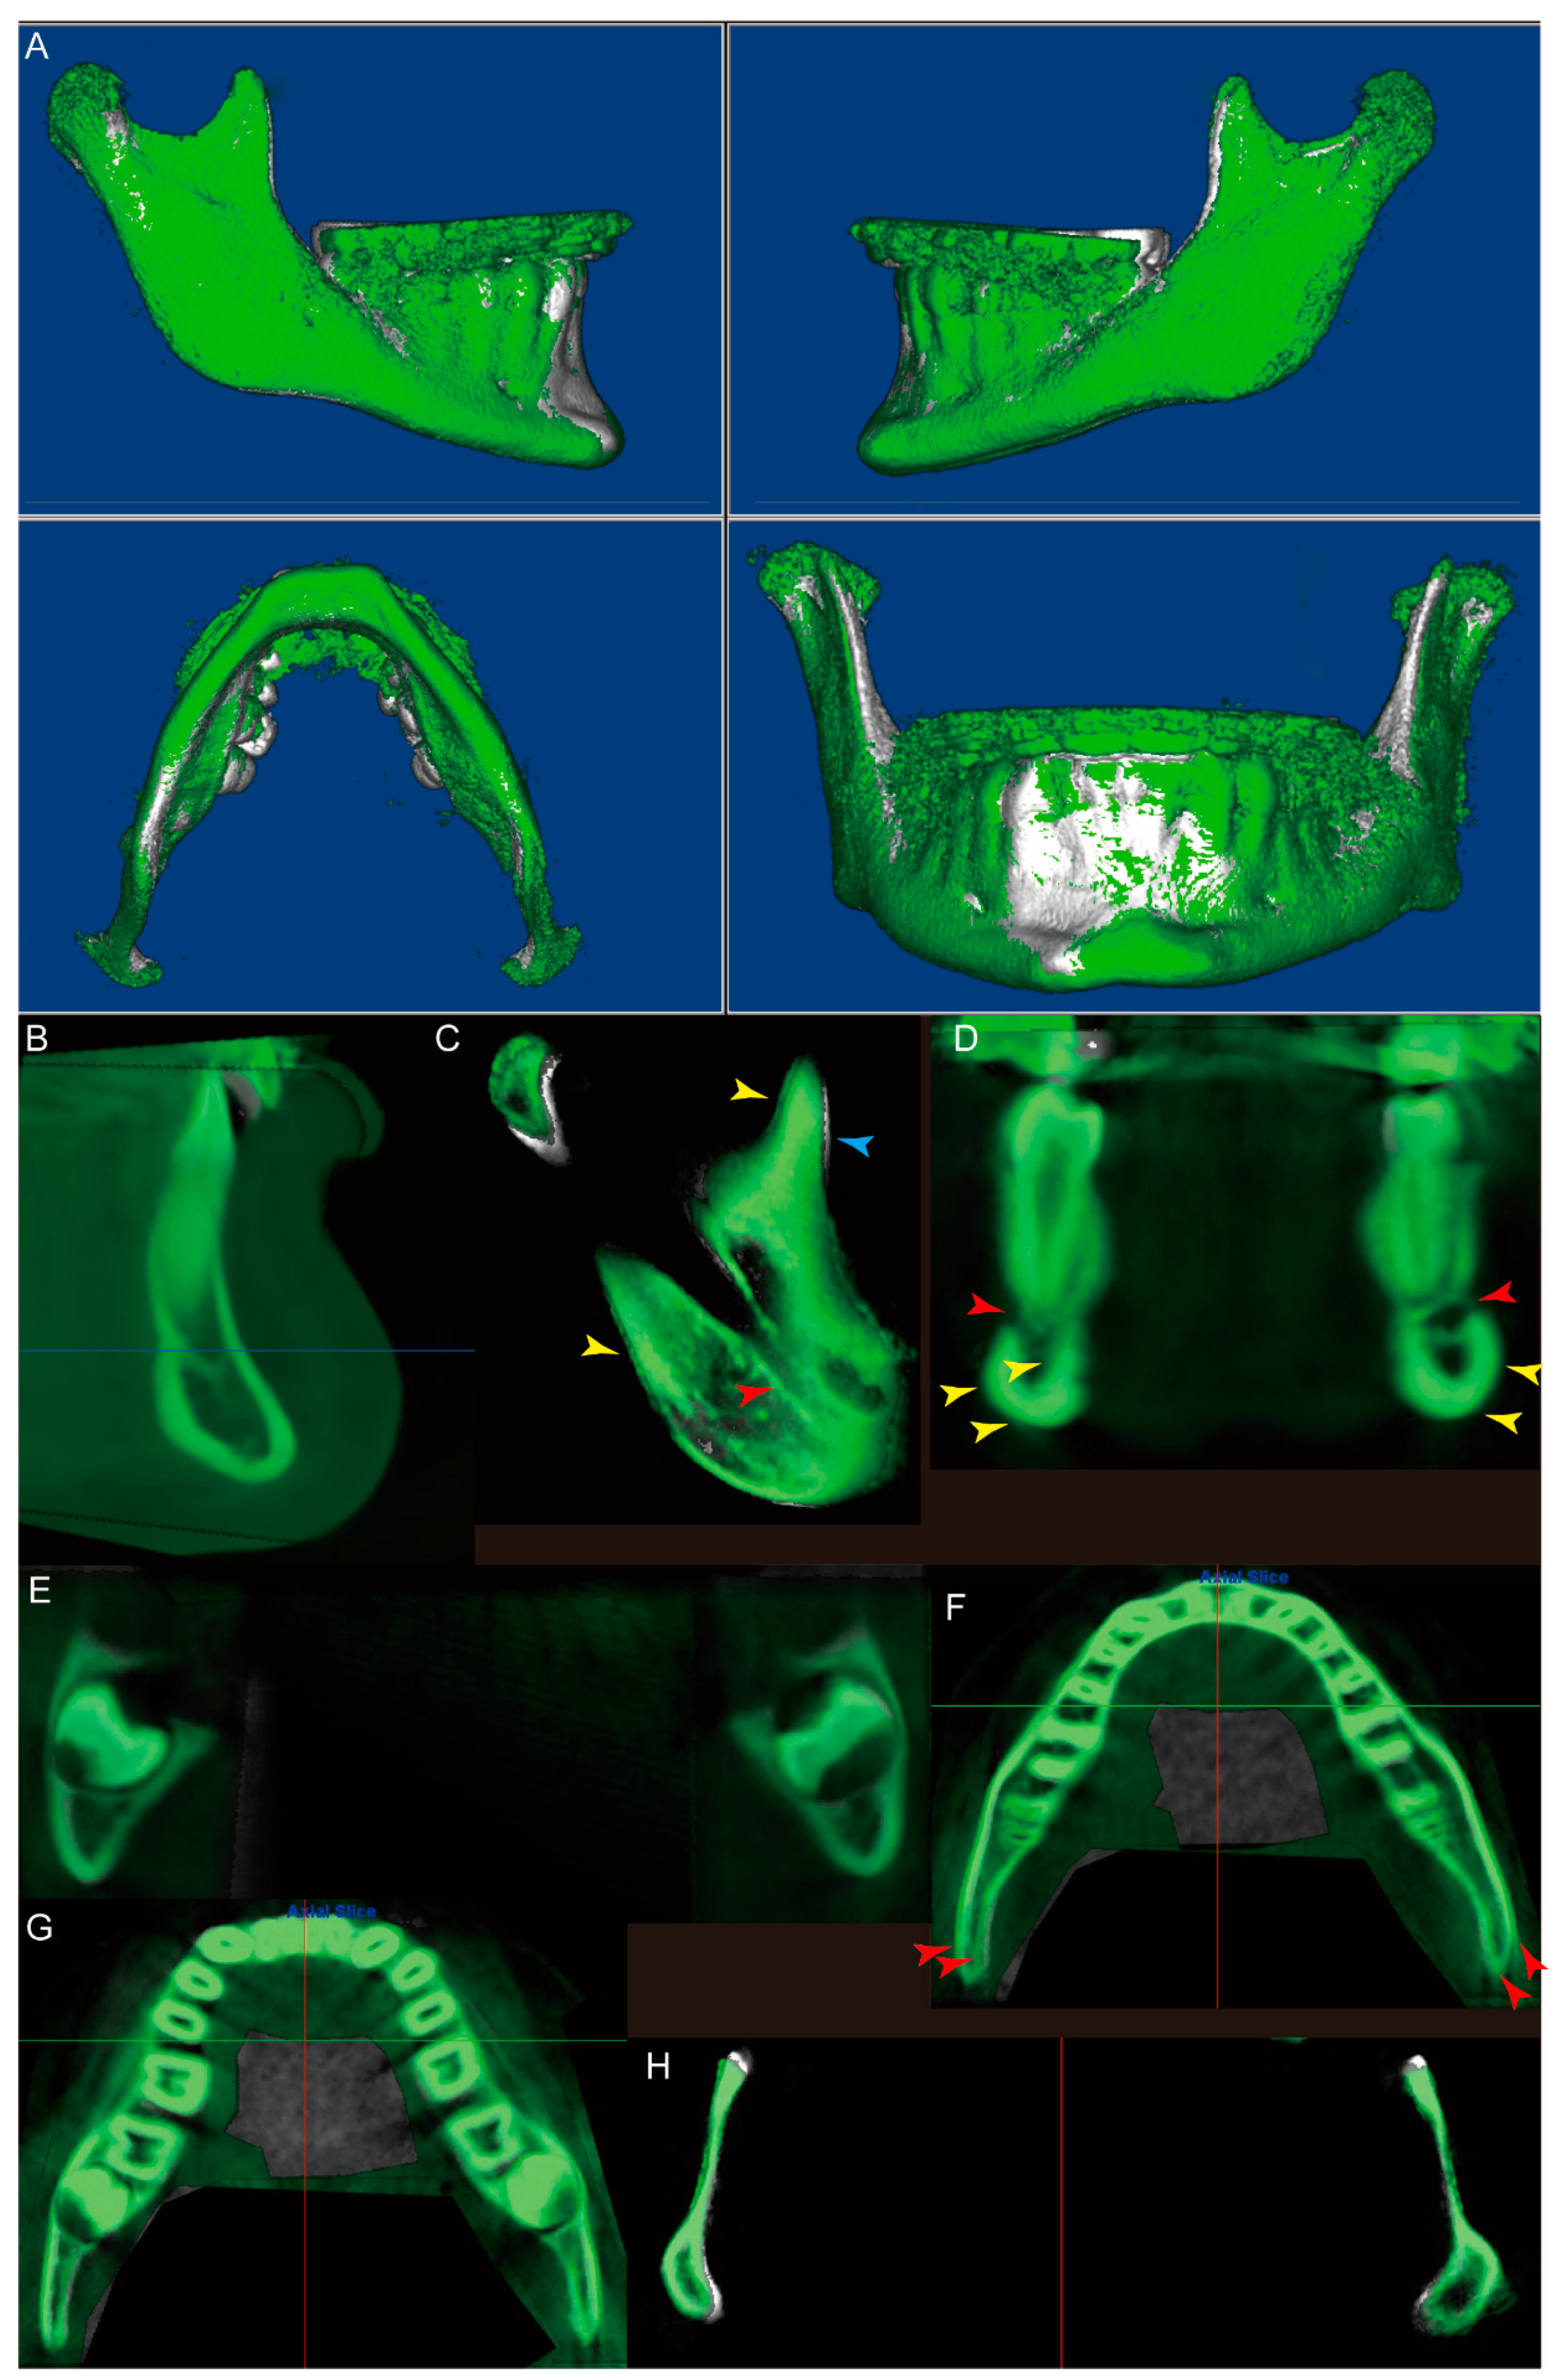

- Orient the CBCT to the right oblique view (Figure 1E), enlarge the CBCT, and change the “Seg Volumes” to identify the lower and upper density values in the appropriate range to differentiate the condyle from the surrounding structures (Figure 1F). This adjustment will produce a translucent view of the right condyle (orange arrow), glenoid fossa (yellow arrow), and remaining maxillary structures (Figure 1G). Sculpt the glenoid fossa along the inferior border and remaining maxillary structures.

- Repeat step 4 for the left condyle with the CBCT oriented to the left oblique view.

- (7)

- (8)